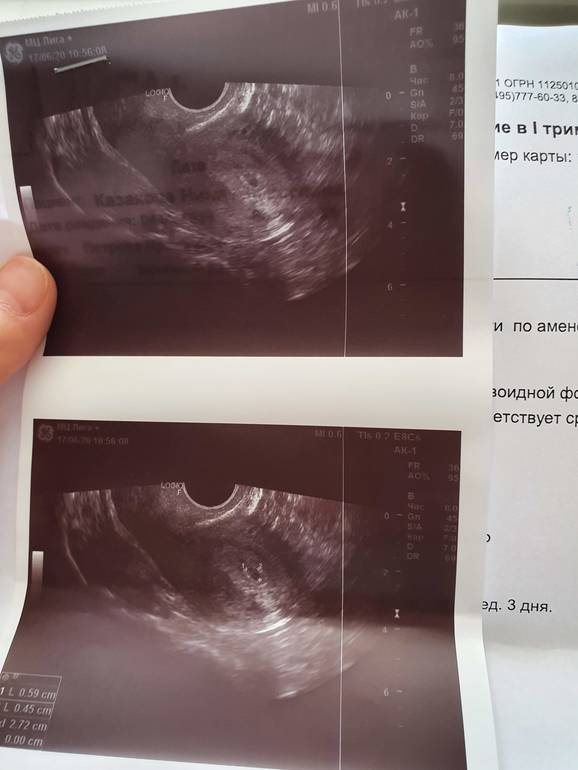

Нормальное плодное яйцо :) для 18 дпо